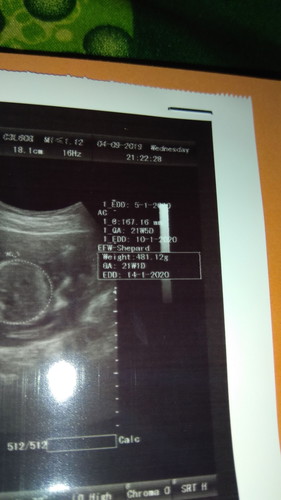

Bener bener tadi gag puas ama dokternya soalnya d tanya hanya bilang bagus... Ada yg maksut gag ya kenapa usia kandungannya beda atas ama bawah.. Yang bner mana ya.. Terus peekiraan lahir jg beda Ada yg maksut gag ya knp bgtu

Memang begitu bun kalau di usg pasti beda antara lingkar kepala sama lingkar perut.itu yg bikin jadi beda HPLnya juga . Saya aja bgtu bun . Makin gede perut HPL makin jauh . Kan dari hpl HPHT saya tgl 7 September, nah skrg 39w4d saya usg HPLnya jadi tgl 24 September (menurut lingkar perut) kalo menurut lingkar kepala HPL malah jadi tgl 11 oktober kan malah makin jauh bgt. Tapi biasanya yg lebih akurat itu yg sesuai HPHT bun .

Beda2 itu krn usg kan ngitungnya berdasarkan panjang tangan, kaki, pelipis, ukuran perut baby bun. Klo mau tau hpl, ikutin berdasarkan hpht aja atau usg paling awal.

Atas bawah gpp beda asal jgn lbh dari 2 minggu. Ac itu usia khmilan bdsrkn ukuran badan. Klo bpd berdsrkan uk kepala bayi

Perkiraan lahir memang beda² itu dilihat dari lingkar kepala panjang badan dll. Yang mendekati akurat USG tm1 ya